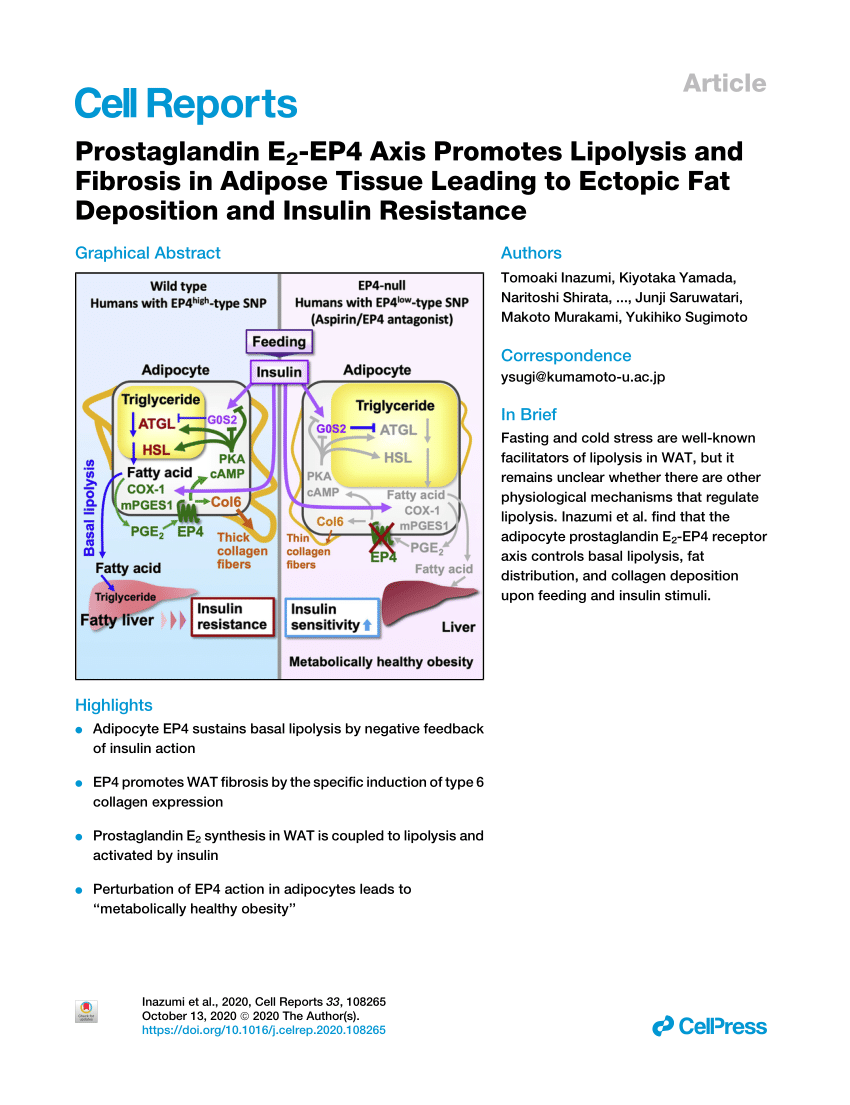

Prostaglandins are inflammatory mediators derived from dietary polyunsaturated fats, which directly drive processes like:

- Stress

- Pain

- Metabolic suppression

- Estrogen production

Just to name a few, which can drive all types of issues, from mood to energy problems.

Critically, prostaglandins promote the release of fat from the fat tissue.

While this may sound like a good thing, excessive dumping of these lipids into the blood contribute directly to

- Insulin resistance

- Organ toxicity

Aspirin counteracts this process.

While this may sound like a good thing, excessive dumping of these lipids into the blood contribute directly to

- Insulin resistance

- Organ toxicity

Aspirin counteracts this process.